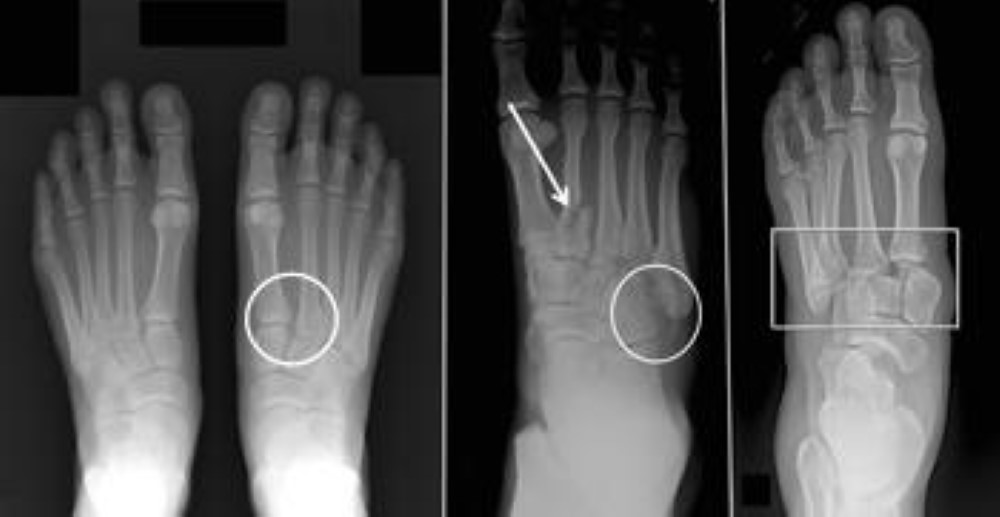

Different types of Lisfranc injuries

(Left) A subtle injury to the midfoot with widening between the first and second metatarsals (circle), compared with the normal foot on the left. (Center) A fracture of the second metatarsal (arrow) and a fracture of the cuboid (circle). (Right) A very severe injury of the foot from a high-energy event. It has resulted in a complete dislocation of the entire midfoot (box). Because no bones have been broken, fusion may be recommended, given the high risk for future arthritis.